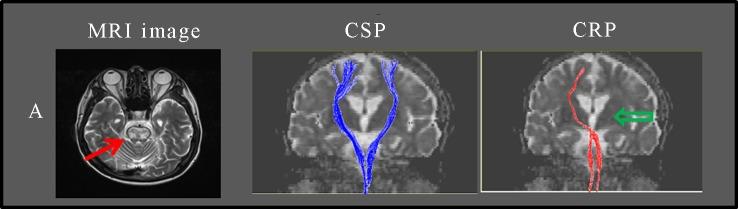

[Purpose] Central pontine demyelination is a common osmotic demyelination syndrome. Typically, central pontine demyelination shows high signal intensity with demyelination in the mid-pons. Despite severe imaging findings, patients usually recover. This study investigated the integrity of the corticospinal tract (CST) and corticoreticular pathway (CRP) in patients at 12 months after the onset of central pontine demyelination. [Participants and Methods] This retrospective cross-sectional observational study assessed two patients with central pontine demyelination, who were ultimately able to walk without using an aid or orthosis and to use both hands but with mild residual symptoms. All participants underwent diffusion tensor imaging (DTI) at 12 months after onset. [Results] Both patients had mild ataxia at 12 months after onset. The integrity of the CST was restored in both cases, while the integrity of the CRP recovered partially. [Conclusion] The integrity of the CST and CRP at 12 months after the onset of central pontine demyelination was similar in both cases as well as the recovery status of the hand function and ambulation. These results may be useful in planning therapy for patients with central pontine demyelination.

[目的] 脑桥中央髓鞘溶解症是一种常见的渗透性脱髓鞘综合征。通常,脑桥中央髓鞘溶解症在脑桥中部表现为脱髓鞘的高信号强度。尽管影像学表现严重,但患者通常会康复。本研究调查了脑桥中央髓鞘溶解症发病12个月后患者皮质脊髓束(CST)和皮质网状通路(CRP)的完整性。[参与者与方法] 这项回顾性横断面观察性研究评估了两名脑桥中央髓鞘溶解症患者,他们最终能够无需辅助器具或矫形器行走,且双手功能尚可,但仍有轻度残留症状。所有参与者在发病12个月后接受了扩散张量成像(DTI)检查。[结果] 两名患者在发病12个月后均有轻度共济失调。两例患者的CST完整性均得以恢复,而CRP的完整性部分恢复。[结论] 两例脑桥中央髓鞘溶解症患者在发病12个月时CST和CRP的完整性以及手部功能和行走能力的恢复状况相似。这些结果可能有助于为脑桥中央髓鞘溶解症患者制定治疗方案。